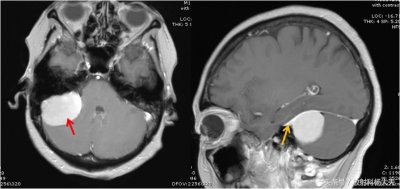

千变万化的影像征象系列(4):脑膜尾征

千变万化的影像征象系列(4):脑膜尾征 医学影像,就是医生靠分析片子上(包括X线,CT,MRI及PETCT等) 的各种表现(征象),结合病人的临床表现,化验检查等来进行推理,推测病...